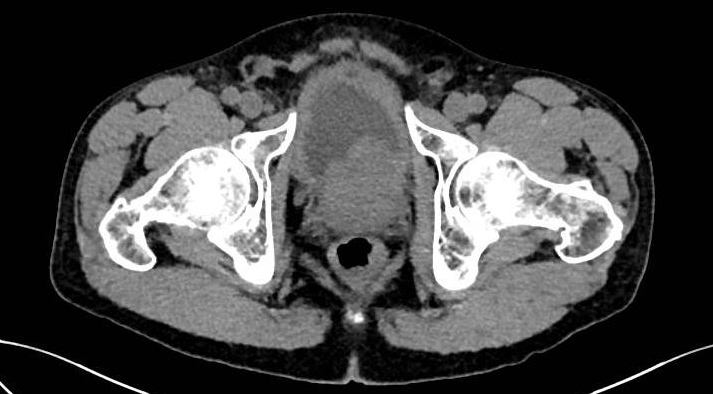

Un scanner sans injection est réalisé.

Question 8 : Parmi les propositions suivantes, lesquelles sont justes au vu des résultats du scanner ?

Le scanner montre une uretéro-hydronéphrose bilatérale avec globe vésical et dilatation importante des cavités pyélocalicielles. Sur la coupe axiale, on voit une hypertrophie de la prostate (surtout le lobe médian) compatible avec une hypertrophie bénigne de la prostate. Le diagnostic de cancer ne peut être éliminé mais les données du toucher rectal ne sont pas en faveur.